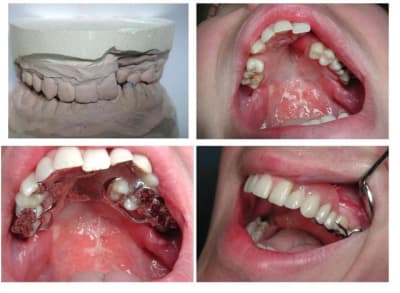

Patiente 50 ans

Syndrome de Down,

Pro-alvéolie maxilaire

Béance inter incisive

Agénésie incisives inf par hyper solicitation

Photos de primaires :

Enregistrement aléatoire d’après érosions visibles

Cadran 3 et 4 désiquilibre par manque d’occlusion

33 précaire à court terme en l’état

Photos de la secondaire inf :

Enregistrement primaire

Confection base résine, prenant appui sur toute partie dentaire supposée non interférente pour enregistrement, prévu s’tents et/ou alu wax

Il s’agit de réaliser une PBM :

Remplaçant l’édentement

Compensant un contact postérieur

Contenant le secteur antérieur fortement sollicité